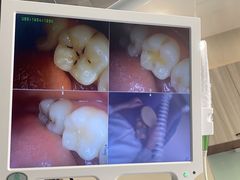

• 医疗健康 齿科 体检中心

口腔齿科 体检中心 医院 药店 中医 宠物医院 整形 妇幼医院 其他医疗